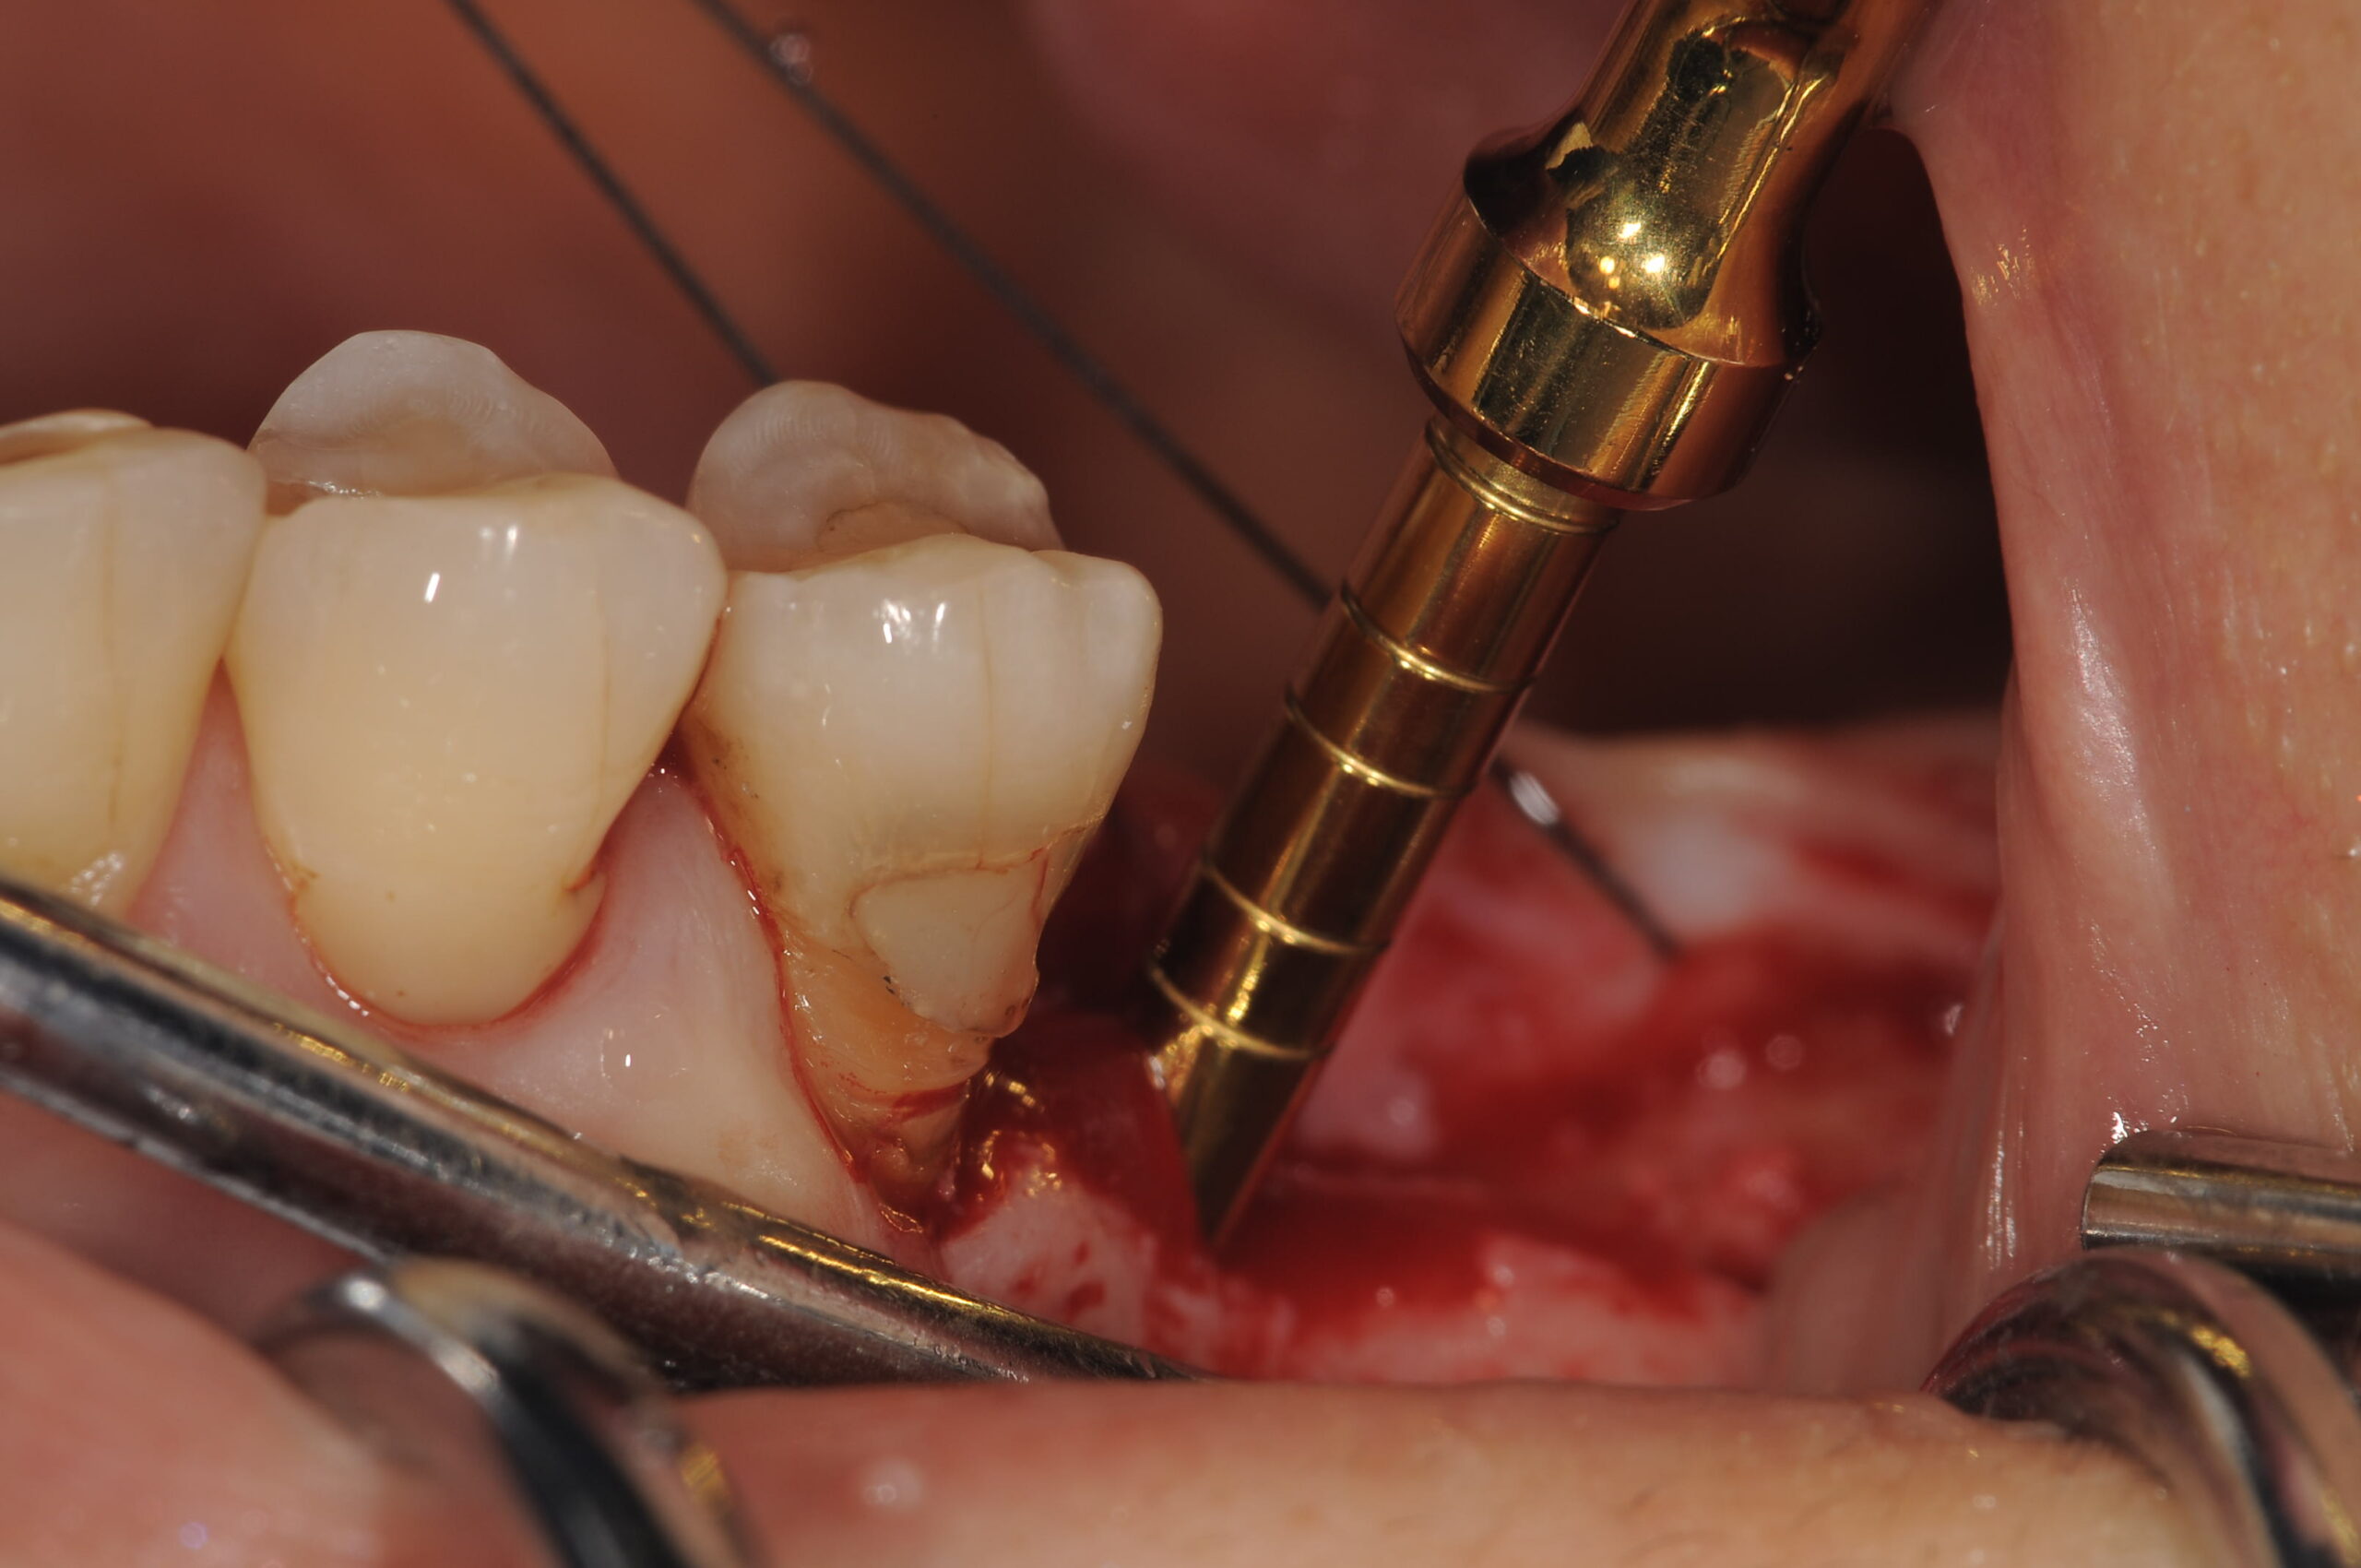

オステオトームテクニックでソケットリフトをしていきます。

骨隆起を避けてソケットリフトでシュナイダー膜を挙上するのですが、あまり骨隆起に近いとうまく粘膜が剥離できない可能性があるので、6番は極力近心部位に、7番は挙上量を少なくするために8mmのショートインプラントを用いました。